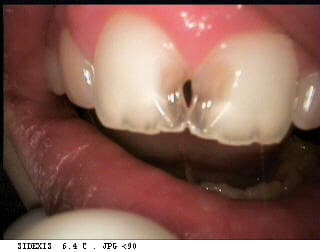

voici le fils d'un couple d'amis que j'ai vu il y a quelques années. vous pouvez constater le développement de la lésion avec le temps et la finesse des dents.

le gamin a 12-13 ans.

Par contre, ce qui est particulièrement surprenant chez un gamin de 12-13 ans c'est qu'on distingue de manière très nette les 3 lobes du bord triturant.

il semble(photo du milieu) y avoir une supraclusie importante et une usure des bords incisifs qui en st devenus transparents

quant aux lesions cela ne ressemble pas à des lesions carieuses:aspect lisse,poli, brillant

l'occlusion n'est pas en jeu,les surfaces palatines paraissent intact,les lesions sont vestibulaires.

comme ploc(coucou ,je ne fais que passer:),je pencherais pour une erosion mecanique,une mauvaise habitude du style se coincer ou frotter quelque chose entre les 11 et 21(a la premiere photo,l'incisive droite a deja son bord mesial incurve)

Avec la descente des canines, les incisives se sont rapprochees,le diasteme a disparu mais pas la mauvaise habitude,l'usure se continue sur les faces vestibulaires.